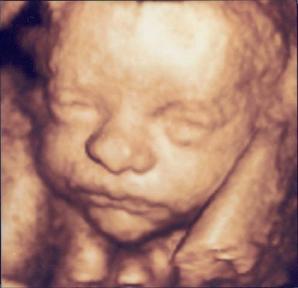

L’ECOGRAFIA 3D E 4D

L’ecografia tridimensionale è il risultato dell’integrazione dei principi dell’ecografia bidimensionale, le scansioni ottenute secondo piani trasversali, longitudinali e obliqui vengono ricostruite tridimensionalmente attraverso l’elaborazione computerizzata in modo da riprodurre l’organo, l’arto o le parti fetali da studiare.

Quando si posiziona sull’addome una sonda dedicata per questo tipo di esame e si avvia la modalità 3D/4D l’apparecchio ecografico acquisisce immediatamente il volume campione con tutti i piani di sezione , li rielabora in tempo reale ed attraverso un processo noto come “ rendering” riproduce delle immagini che sono molto simili alla realtà.

La modalità 4D consente di esplorare l’aspetto tridimensionale di un organo, o del feto nel tempo, seguendo i movimenti in tempo reale. Si vedrà quindi in diretta, il feto muovere le manine, succhiarsi il dito, giocherellare con il cordone ombelicale etc.

Le sonde impiegate sono in grado di acquisire circa 25 –30 fotogrammi al secondo senza movimento della sonda; ne consegue una immediatezza nella visualizzazione dei particolari tridimensionali fetali. Se il 3D è paragonabile ad una fotografia convenzionale il 4D è paragonabile ad una ripresa video.

L’ecografia 3D non è assolutamente un esame di routine.

La sua esecuzione è piuttosto indaginosa rispetto ad una ecografia ostetrica bidimensionale, è condizionata da vari fattori che ne possono compromettere la riuscita. La posizione del feto è, ad esempio, cruciale se si vogliono ottenere immagini del volto fetale, ovvero il feto deve rivolgere il volto verso l’addome della mamma; è necessaria una certa quantità di liquido amniotico che si comporti da interfaccia per decodificare le immagini, la sua scarsità o la vicinanza con altre strutture può cearare artefatti che preoccupano i genitori; l’ecogenicità dei tessuti della donna influenza molto le qualità delle immagini che si ottengono; è talvolta possibile dover rimandare l’esame in un momento più favorevole per un’altra seduta.

Il suo scopo è ovviamente clinico-diagnostico come approfondimento di elevata specializzazione ed in tal caso viene impiegato come ausilio o complemento nella definizione e caratterizzazione di un difetto congenito (in caso ad esempio di difetti del viso, delle mani, dei piedi della colonna vertebrale) utilizzando la macchina in tutte le sue modalità (volume mode sezioni multiplanari e modalità trasparente).

In tutti gli altri casi rappresenta più una occasione per vedere il proprio bambino nel suo percorso di sviluppo intrauterino; la ricostruzione attraverso la modalità VOLUME è una specie di calco e riproduce una vera immagine tridimensionale del viso, delle mani ecc, fornendo una lettura della superficie del bambino a contatto con il liquido amniotico permettendo ai genitori di osservarne le fattezze del volto, spiarne i movimenti, e se fortunati registrare uno sbadiglio o una smorfia. L’esame è generalmente fonte di una forte emozione per i genitori.

Alla luce delle conoscenze mediche attuali, l’ecografia 3D - 4D è innocua come l’ecografia bidimensionale standard. Non vengono infatti utilizzate potenze differenti, cambia solo il modo di rappresentazione dell’immagine Deve risultare tuttavia ben chiaro che, in queste circostanze, l’esame perde valore diagnostico, nel senso che non è mirato alla valutazione anatomica convenzionale di tutti gli organi fetali ed all’esclusione di eventuali difetti congeniti.